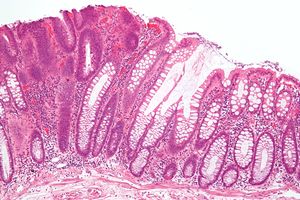

Tubular adenoma 2 intermed mag.jpg

صورة مجهرية لورم غدي أنبوبي (يسار الصورة)، أحد أنواع السلائل القولونية ونذير بسرطان القولون. الأغشية المخاطية القولونية تظهر على يمين الصورة.